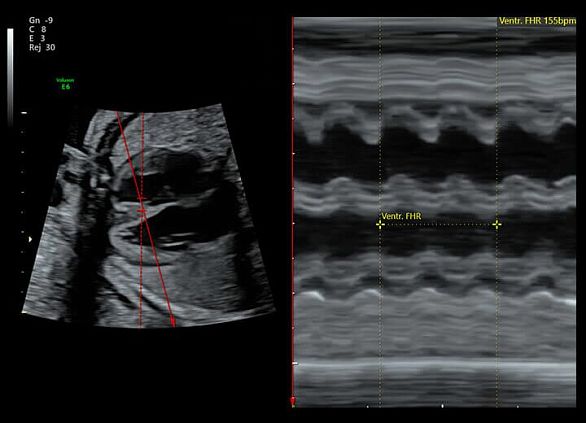

Клинические изображения

УЗИ аппарат Voluson E6 гарантирует превосходное качество визуализации как 2D-режиме, так и при объемной реконструкции в 3D/4D режиме, а также при цветовом допплеровском картировании. Благодаря инновационным инструментам автоматизации и интуитивному интерфейсу пользователя достигается существенное сокращение времени исследований, упрощается труд врача, снижается утомляемость и повышается общая производительность и пропускная способность.

УЗИ аппарат Voluson E6 гарантирует превосходное качество визуализации как 2D-режиме, так и при объемной реконструкции в 3D/4D режиме, а также при цветовом допплеровском картировании. Благодаря инновационным инструментам автоматизации и интуитивному интерфейсу пользователя достигается существенное сокращение времени исследований, упрощается труд врача, снижается утомляемость и повышается общая производительность и пропускная способность.